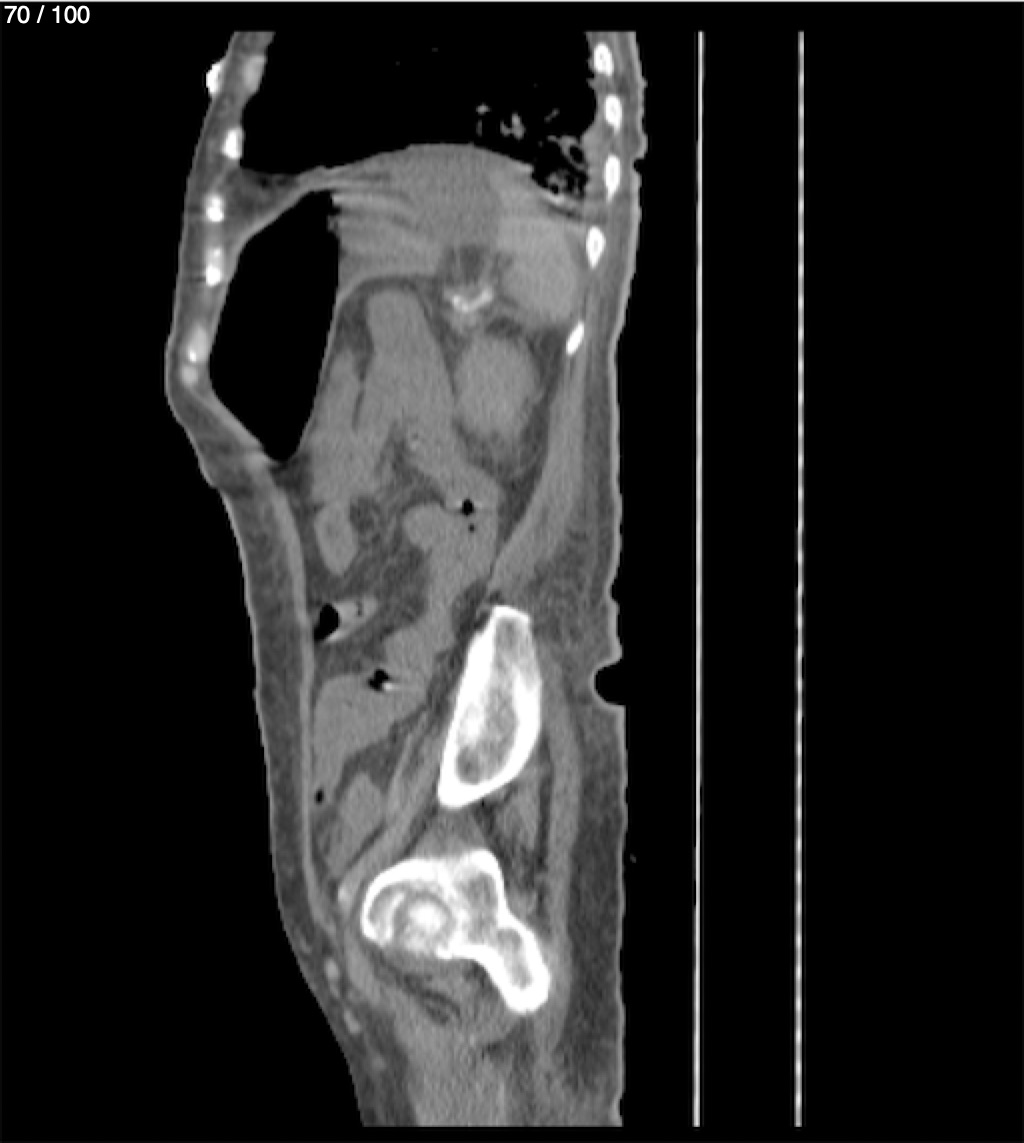

Hilda Geronimo Mendez 60A - T.C Abdomen Simple